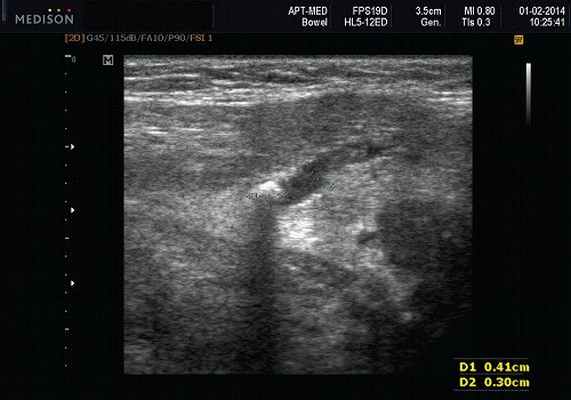

Рис. 3. Сиаладенит правой поднижнечелюстной слюнной железы.

- обструктивные сиаладениты, развивающиеся при затруднении оттока слюны при обструкции выводного протока камнем (рис. 5-7) или сгустившимся секретом, а также вследствие рубцового стеноза протока. По распространенности процесса различают очаговый, диффузный сиаладениты и сиалодохит - воспаление выводного протока. Течение процесса может быть острым и хроническим;

Рис. 5. Камень протока поднижнечелюстной слюнной железы.

Рис. 6. Камень в паренхиме поднижнечелюстной слюнной железы.

Рис. 7. Камень в протоке поднижнечелюстной слюнной железы.